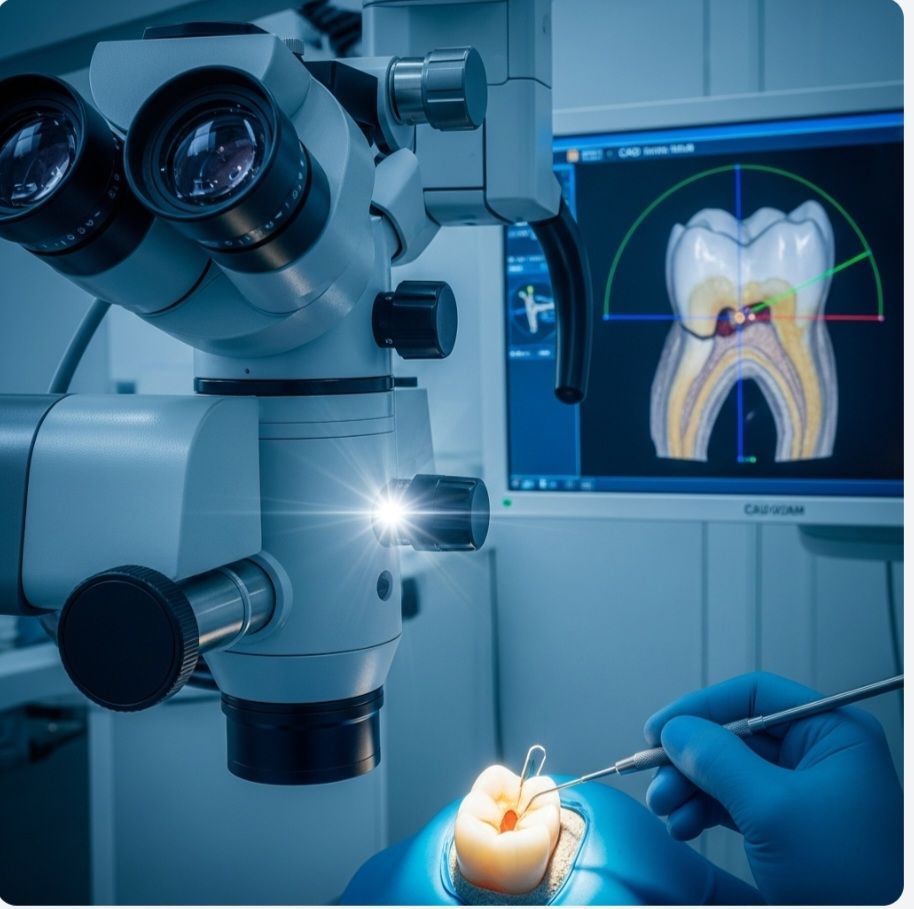

تعد تقنية CAD/CAM (Computer-Aided Design / Computer-Aided Manufacturing) الركيزة الأساسية التي انتقل بها طب الأسنان من مرحلة الحرفية اليدوية إلى مرحلة الهندسة الرقمية الدقيقة. في اليمن، بدأ هذا التحول يكتسب زخماً كبيراً مع افتتاح مراكز متخصصة تمتلك مختبرات رقمية داخلية، مما قلل من الاعتماد على المختبرات الخارجية وضمن رقابة صارمة على الجودة.

يبرز مركز زركون كأول مركز تقني في الجمهورية اليمنية يستخدم تقنيات الماسح الضوئي ثلاثي الأبعاد والطباعة ثلاثية الأبعاد بشكل متكامل. إن الحصول على شهادة الجودة العالمية ISO 9001:2015 لم يكن مجرد إنجاز إداري، بل هو انعكاس لالتزام المركز بمعايير دقيقة في كل مرحلة من مراحل العلاج، بدءاً من التشخيص الرقمي وصولاً إلى التركيب النهائي.

تعتمد الزراعة الرقمية في مركز زركون على دمج صور الأشعة المقطعية ثلاثية الأبعاد (CBCT) مع المسح الرقمي للفم. يتيح ذلك للأطباء تصميم "دليل جراحي" يحدد بدقة مليمترية مكان وزاوية وضع الغرسة.